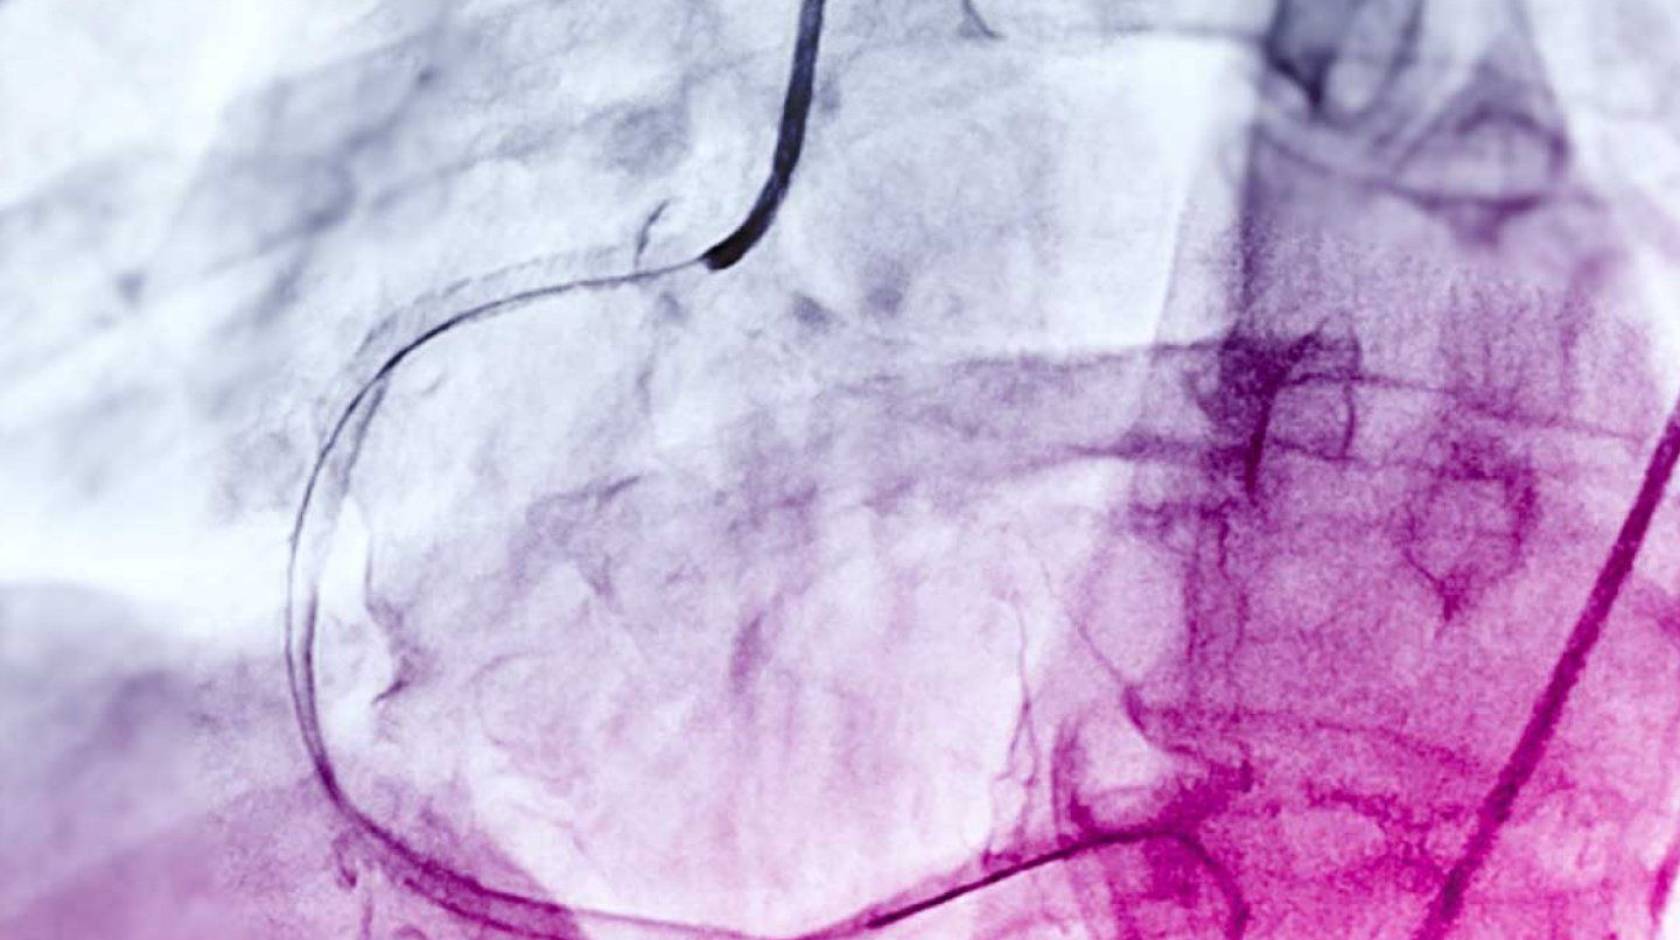

Angiograms, much like this above, could one day be used to diagnose more serious cardiac issues without further risky testing.

Physicians commonly use a test called a coronary angiogram to diagnose the condition. As part of angiograms, physicians inject a special dye into the main vessels that feed the heart to see how blood flows using x-rays. Angiograms much like this could one day be used to diagnose more serious cardiac issues without further risky testing.